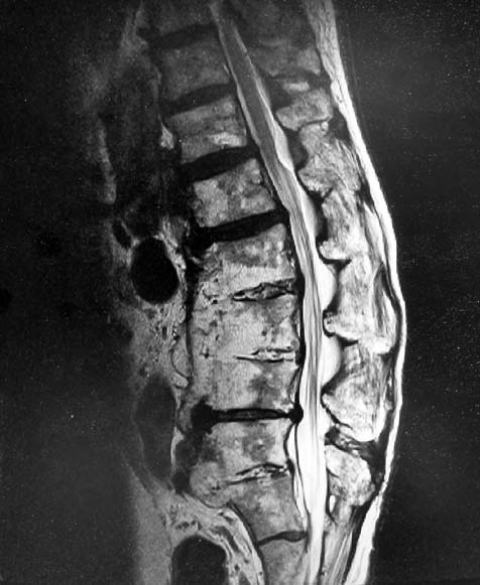

腰椎MRI

骨粗鬆症および古い圧迫骨折があります。この条件ではわかりにくいですがL1レベルでわずかに脊髄が押されている所見があり、整形外科で軽度の脊柱管狭窄と判断されています。